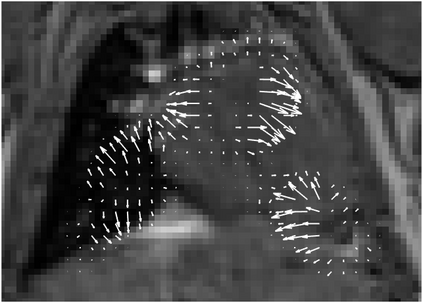

Various imaging modalities allow for time-dependent image reconstructions from measurements where its acquisition also has a time-dependent nature. Magnetic particle imaging (MPI) falls into this class of imaging modalities and it thus also provides a dynamic inverse problem. Without proper consideration of the dynamic behavior, motion artifacts in the reconstruction become an issue. More sophisticated methods need to be developed and applied to the reconstruction of the time-dependent sequences of images. In this context, we investigate the incorporation of motion priors in terms of certain flow-parameter-dependent PDEs in the reconstruction process of time-dependent 3D images in magnetic particle imaging. The present work comprises the method development for a general 3D+time setting for time-dependent linear forward operators, analytical investigation of necessary properties in the MPI forward operator, modeling aspects in dynamic MPI, and extensive numerical experiments on 3D+time imaging including simulated data as well as measurements from a rotation phantom and in-vivo data from a mouse.